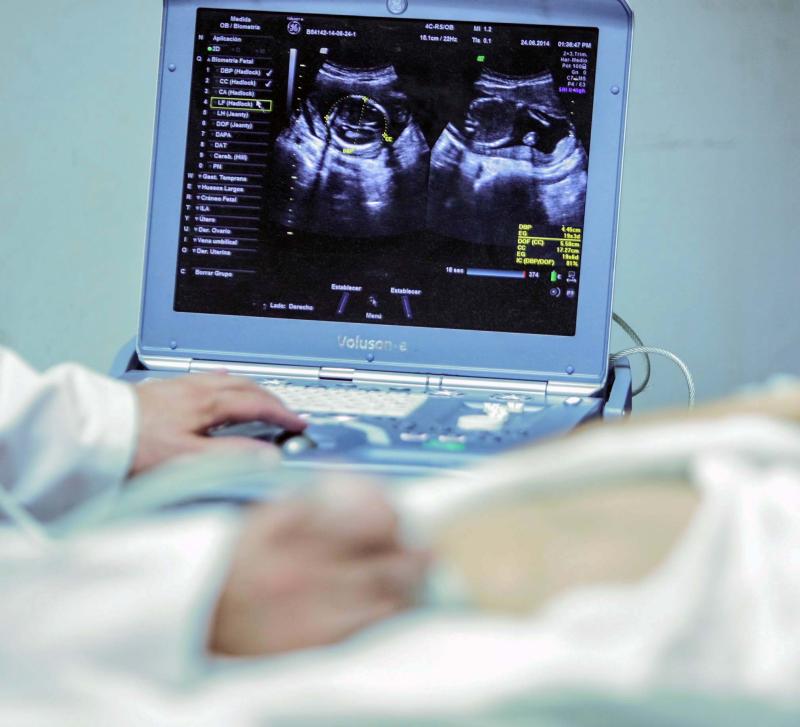

Jalisco se ubica en el quinto lugar nacional de embarazos adolescentes al registrar más de tres mil 300 casos, indicaron especialistas del Hospital Civil de Guadalajara como parte de las actividades de concientización por el Día Nacional de la Prevención del Embarazo no Planeado en Adolescentes, que se conmemora el 26 de septiembre.

“A nivel mundial se presentan 21 millones de embarazadas adolescentes, que van desde los 12 a los 19 años, y es muy importante concientizar porque Jalisco está en quinto lugar a nivel nacional con tres mil 357 casos reportados en el 2024”, resaltó el Ernesto Ledezma Hurtado, jefe del Servicio de Obstetricia del Antiguo Hospital Civil de Guadalajara “Fray Antonio Alcalde”.

El especialista mencionó que en esa institución se atendieron 201 casos de consulta de control prenatal, 105 cesáreas, 151 partos y 406 atenciones psicológicas. Sin embargo, resaltó que es necesario empezar desde las secundarias, e incluso primarias, con la concientización de los embarazos adolescentes no planeados.

Las y los especialistas mencionaron que la edad media de los casos registrados en el Hospital Civil oscila entre 15 y 18 años. No obstante este año también se han reportado ocho pacientes embarazadas de menos de 12 años, 10 de 13 años y 11 de 14 años.

Ledezma Hurtado añadió que este año se reportó un caso de muerte materna en una paciente, y la mayoría de pacientes con embarazos adolescentes no planeados provienen de los municipios de Zapopan, Tlajomulco y Guadalajara.